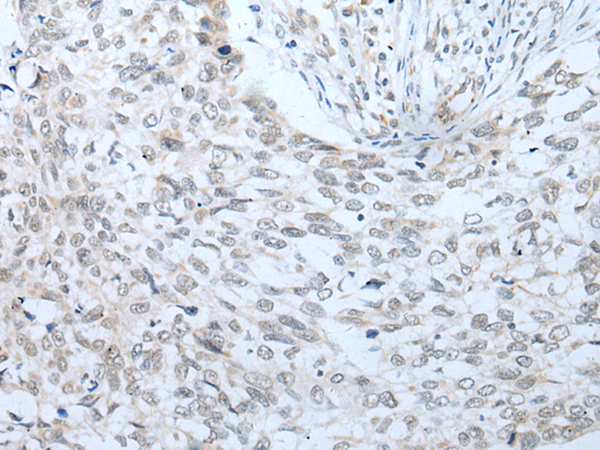

IHC positive control: |

Human lung cancer |

IHC Recommend dilution: |

20-100 |